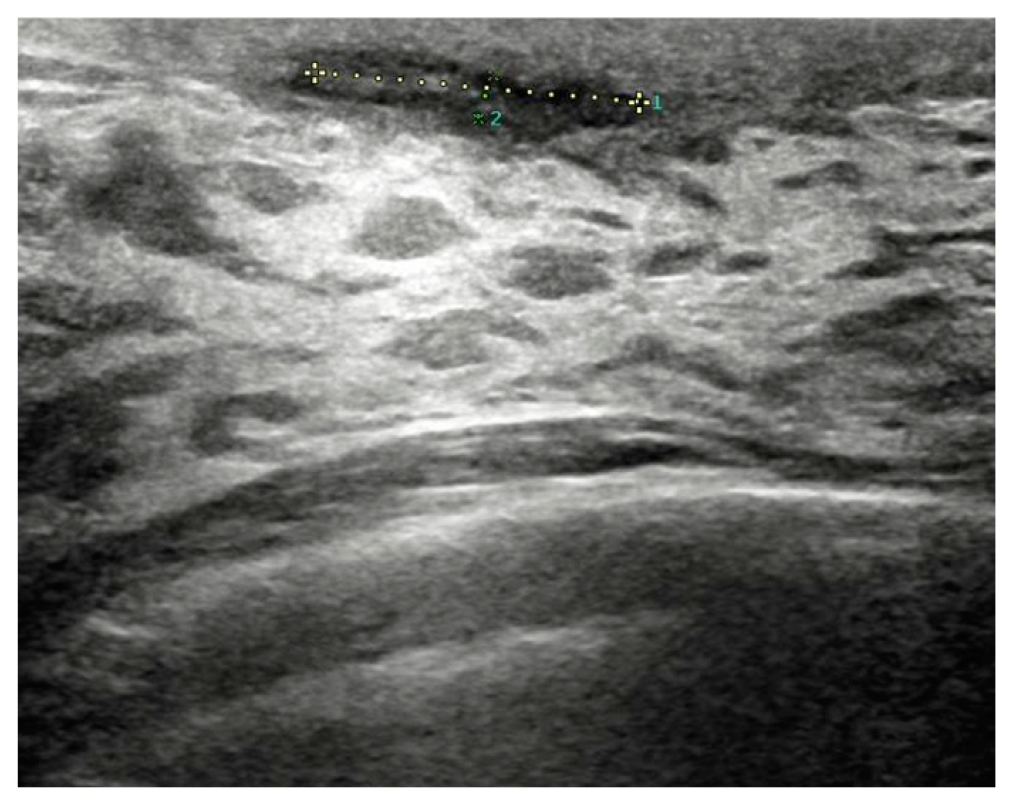

Before surgery, all patients underwent breast ultrasound to assess the presence of an abscess or fistula. Regarding clinical and radiological presentation, 12 patients presented with an abscess in the form of a painful and tender breast mass, with tense and reddened skin but no cutaneous fistula, confirmed by ultrasound (Figure 1, Figure 2 and Figure 3); two patients presented with an abscess associated with periareolar fistula (Figure 4), visible on breast ultrasound; five patients showed signs of a past abscess with negative preoperative ultrasound findings, and among them, one had a fistulous tract without purulent discharge (Table 1). The location of abscesses, fistulas, and their sequelae was the periareolar area in all patients. Additionally, four patients presented with bilateral symptoms. For patients with active abscesses at surgery, the mean size of the abscess cavity was 28.7 mm.

Figure 4. Abscess with a fistula in the periareolar region.